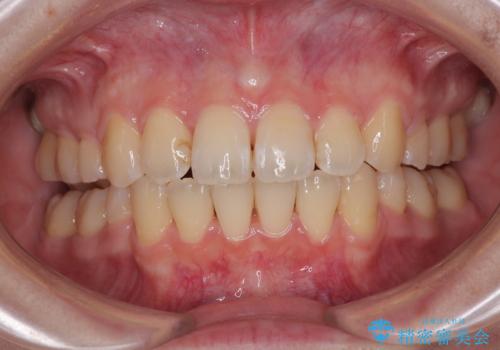

捻れて前に出ている前歯 ワイヤー装置での非抜歯矯正